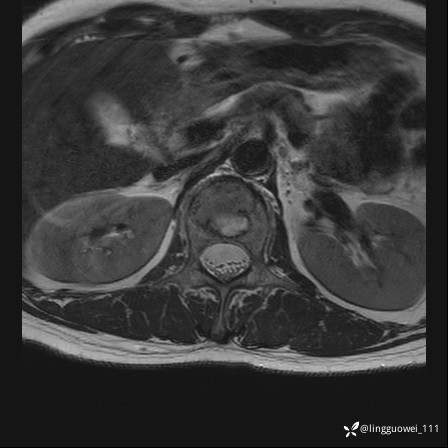

病例女,39岁,腰痛来诊,只有CT可能要鉴别诊断,而MR可以定性吗?

患者性别:女

患者年龄:39岁

主诉:腰痛